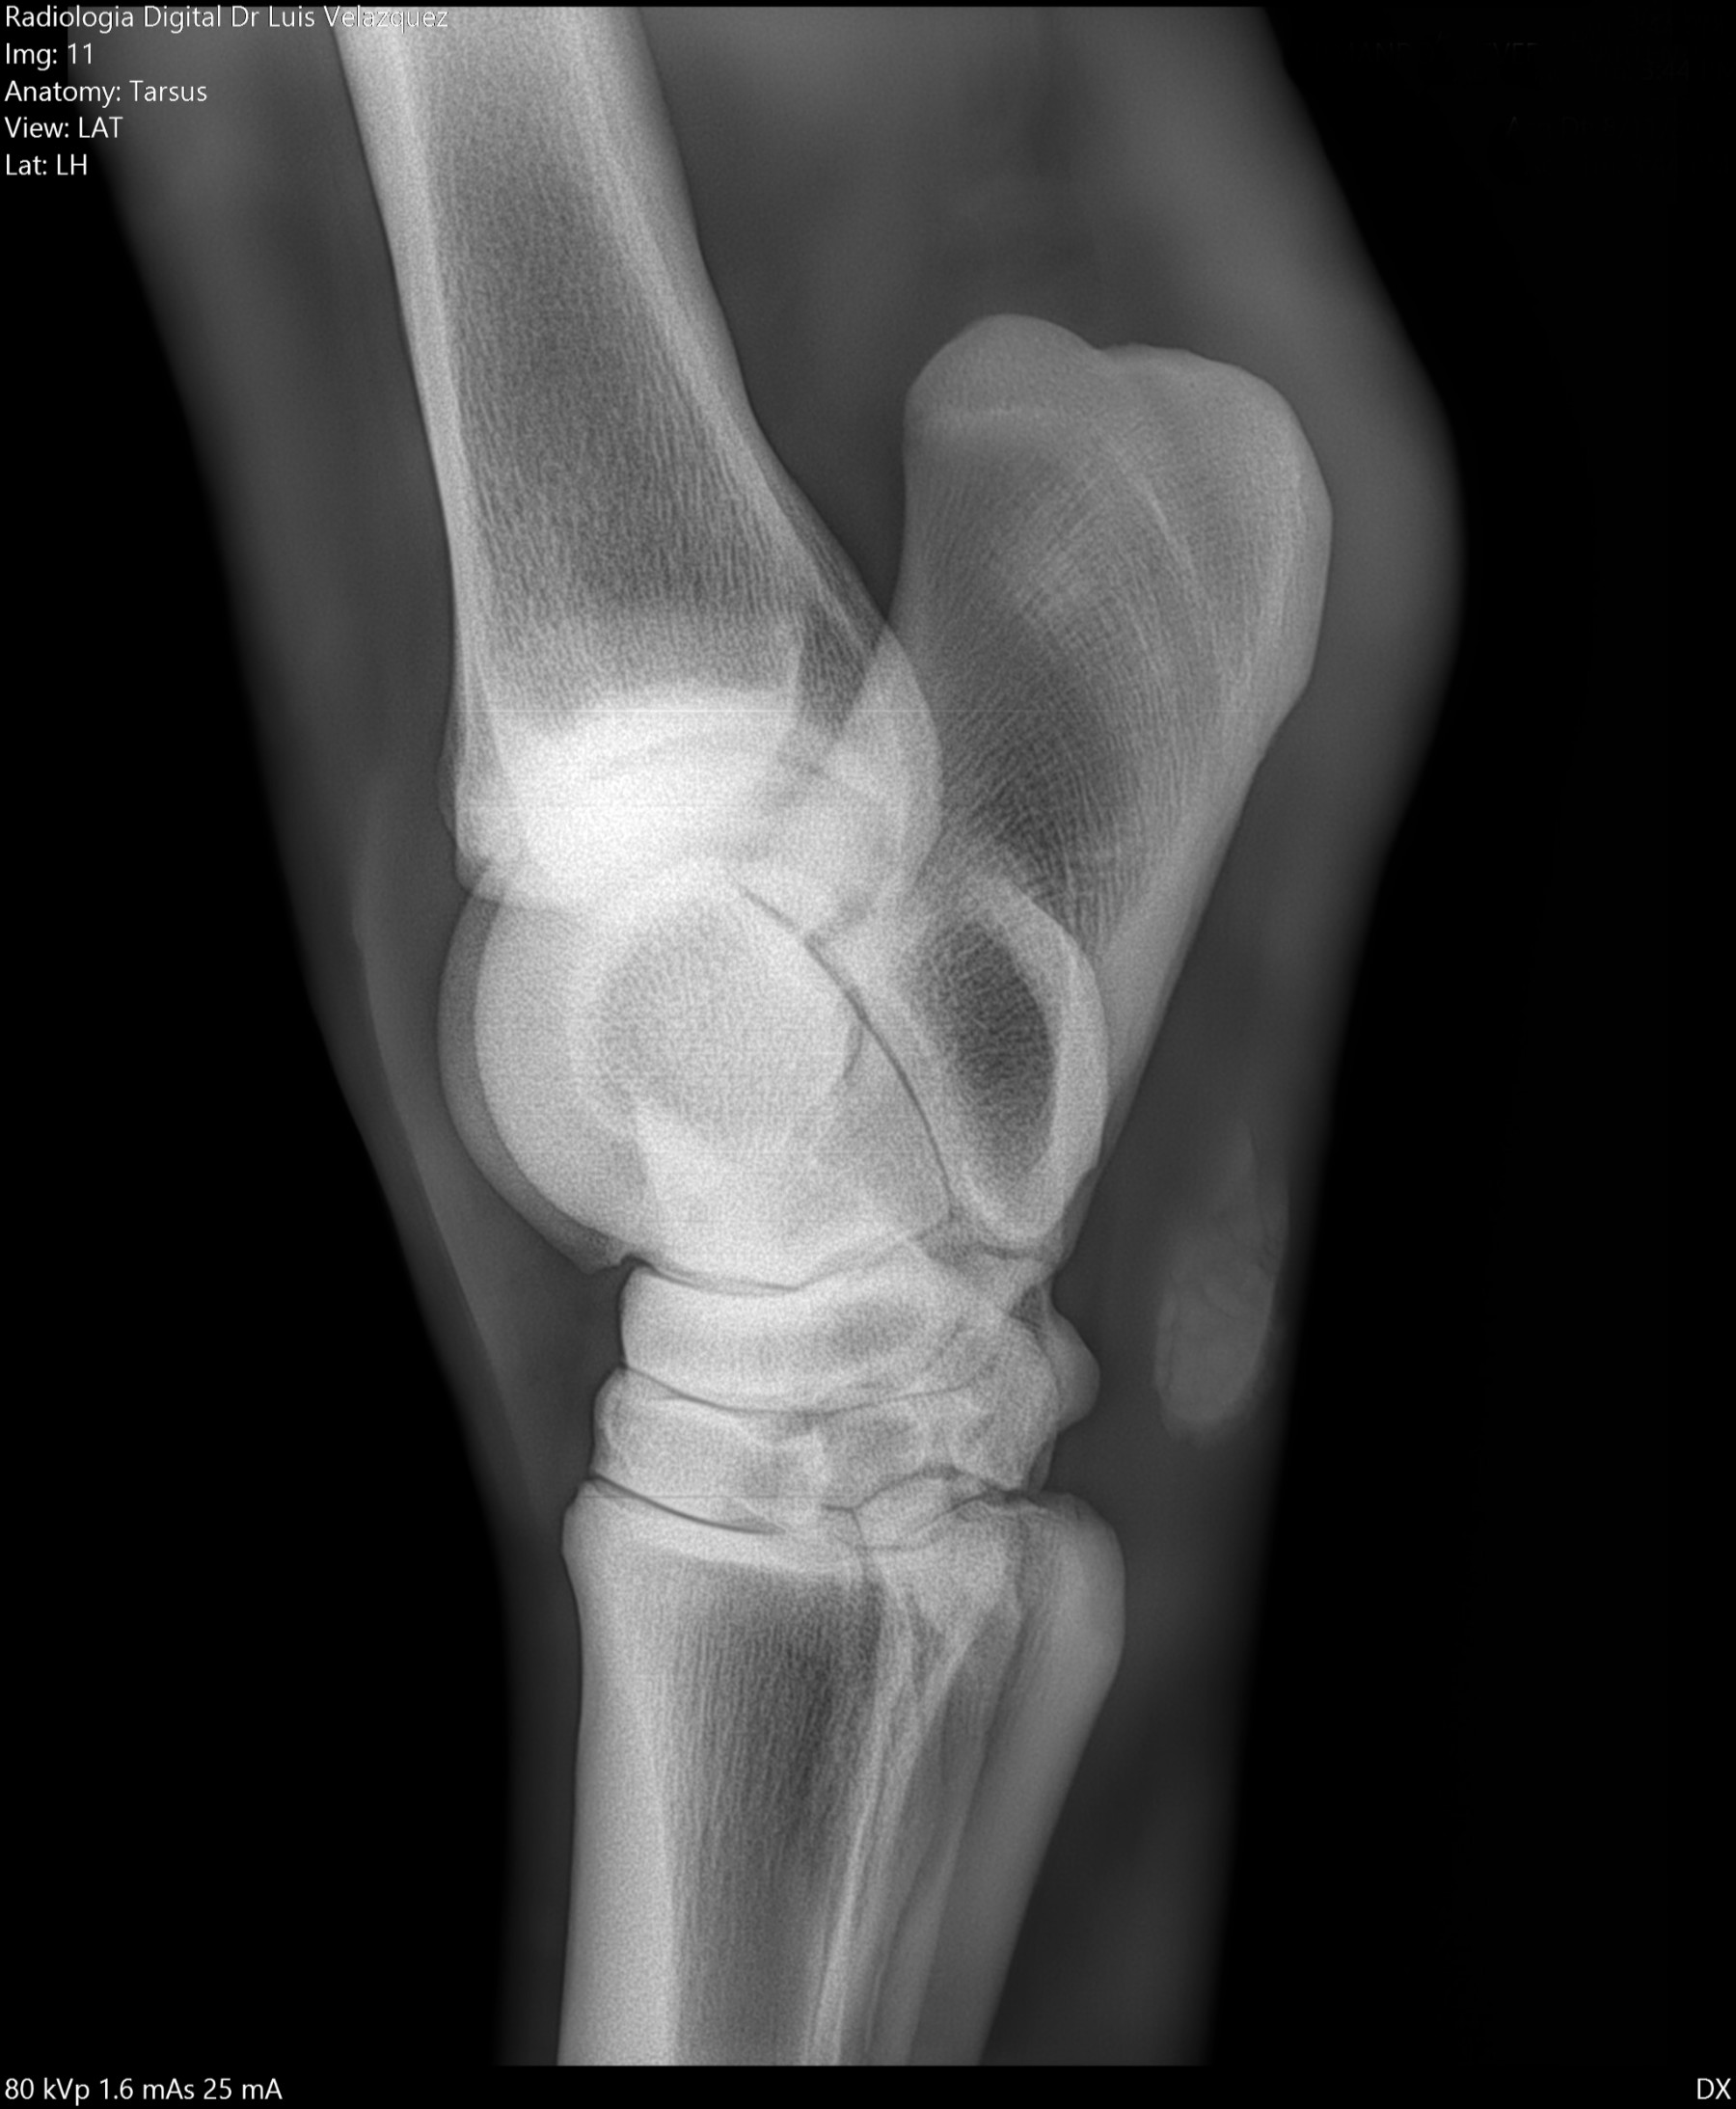

Cambios Térmicos en las Extremidades de Caballos,

Asociados a Golpes y su Evaluación por Termografía.

Los caballos de salto, en competencia, pueden derribar obstáculos y lastimarse. Si se golpean, no siempre claudican. Considerando al calor como un signo de inflamación, se evaluaron los cambios térmicos de 6 áreas de las extremidades torácicas y pelvianas de 23 caballos de salto en nivel de competencia de 1.05 a 1.60 m de altura, por medio de termografía durante 4 días de competencia (N=2208 áreas).